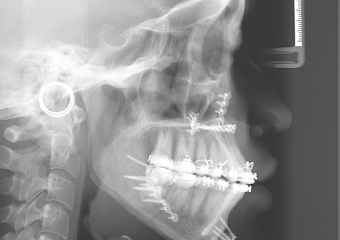

Telerradiografia após a cirurgia - Clínica Cliniface

Telerradiografia após a cirurgia